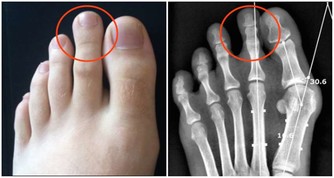

肝臟有問題時————小腿晚上睡覺時容易抽筋。